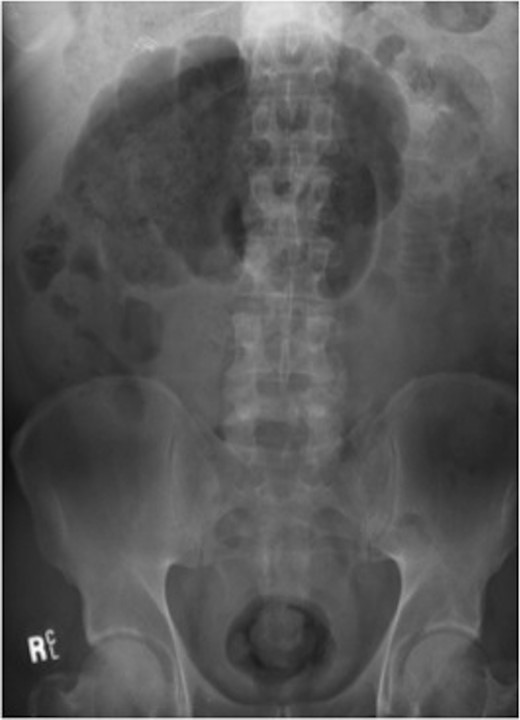

Haemoglobin was 14.9 g/dl and the white cell count (WCC) was 9 × 109/l. Other remarkable laboratory tests included a C-reactive protein (CRP) of 15 mg/l. Urinalysis was normal. The plain X-ray abdomen (AXR) (Fig. 1) revealed dilatation of a focal segment of large bowel with mildly dilated small bowel. Computed tomography (CT scan) of his abdomen reported that the gas-filled viscus is likely to represent the caecum (Fig. 2).

CT of the abdomen (Case 1) demonstrating the gas-filled caecum.